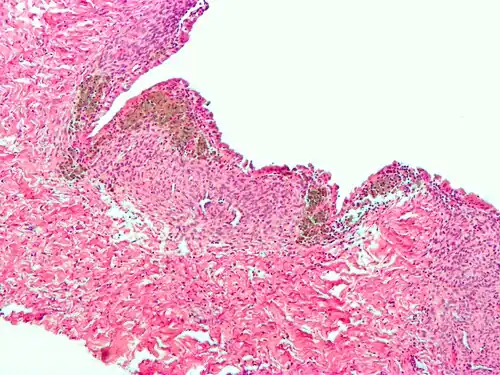

-

Endometriosis, abdominal wall -

Micrograph showing endometriosis (right) and ovarian stroma (left) -

Micrograph of the wall of an endometrioma. All features of endometriosis are present (endometrial glands, endometrial stroma and hemosiderin-laden macrophages).